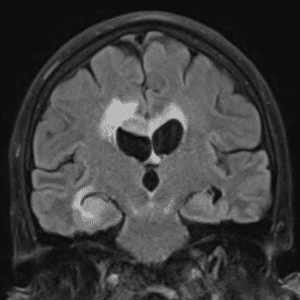

Case #42

Giant cerebral aneurysm